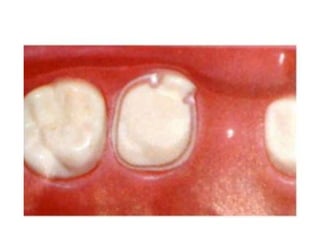

A)Full coverage crown:

It is an extra coronal restoration

that covers all the surfaces of

the prepared clinical crown

Types of crowns: